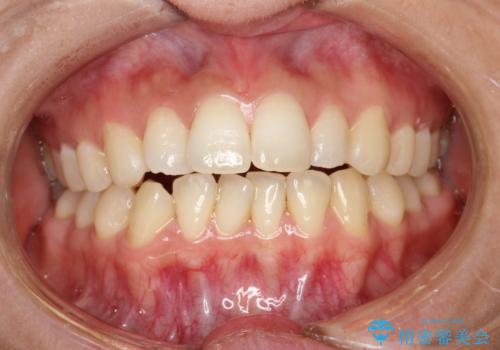

- 出っ歯で口が閉じずらくて、前歯でものかが噛み切れないとのことで来院されました。

上顎の前歯が前方に傾斜して、下顎の前歯と接触していない状態でした。

前歯がしっかり下がることで、上下の前歯があわさり食事もしやすくなったと言っていただきました。